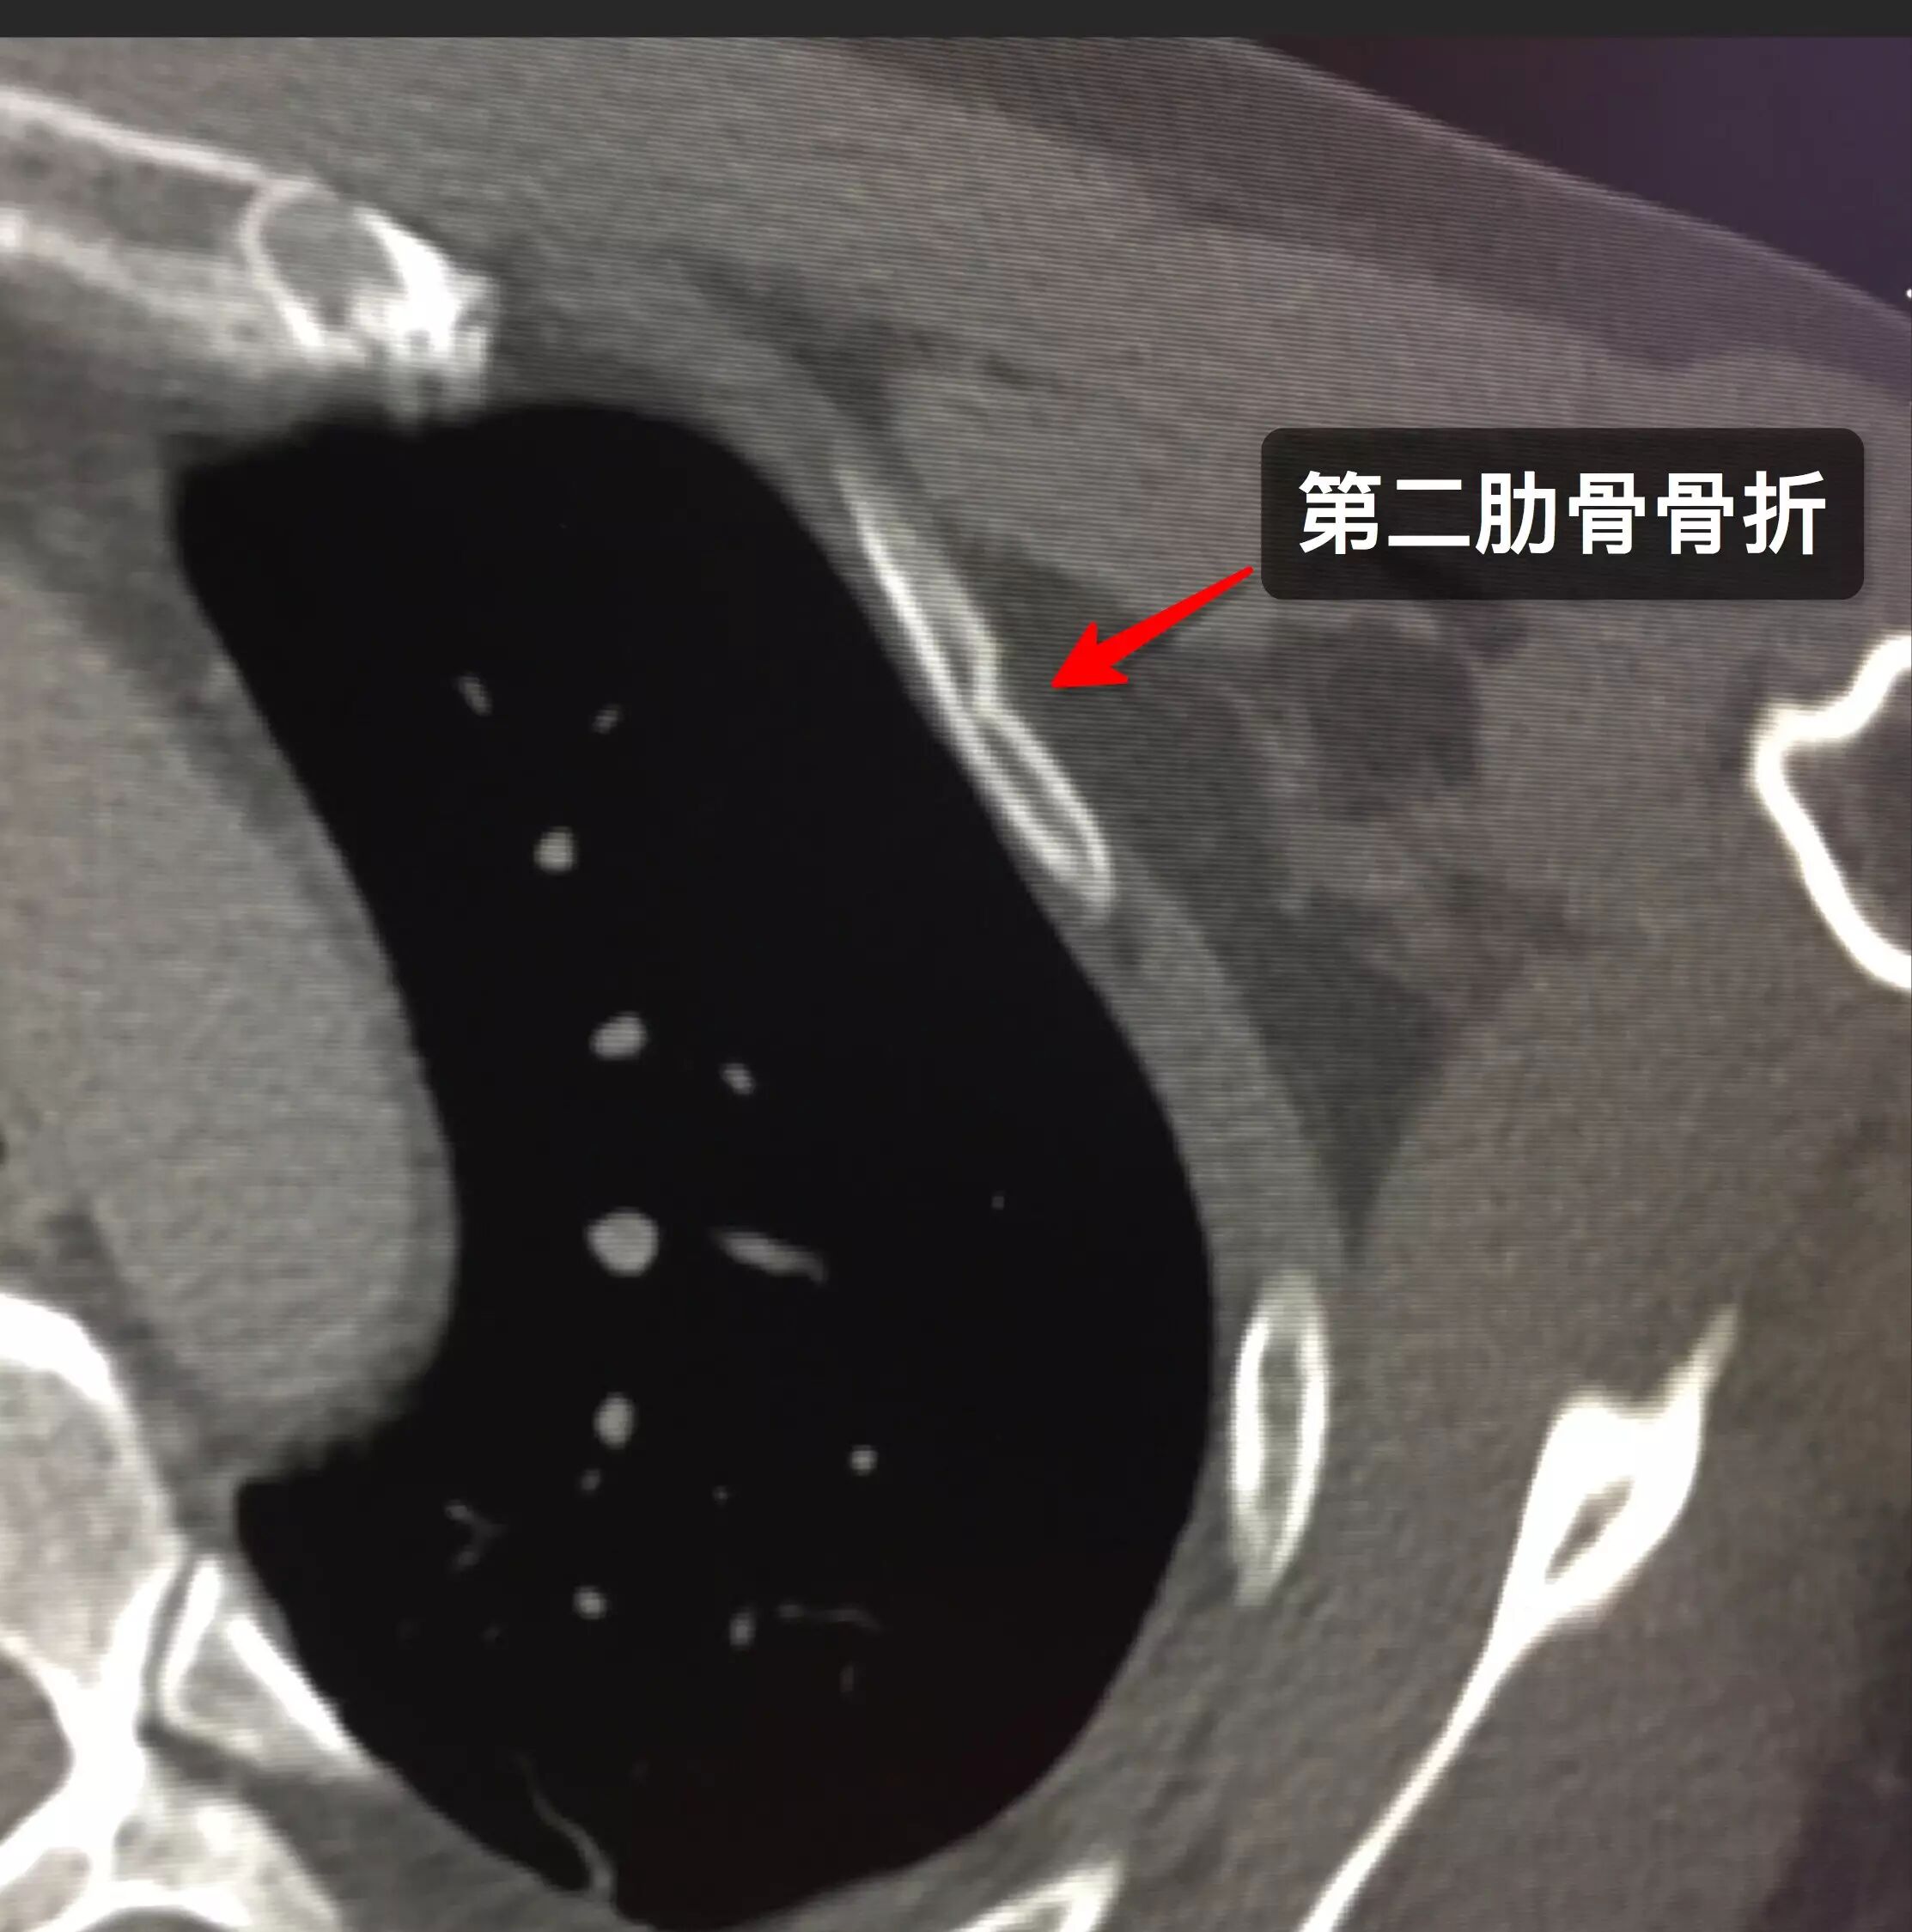

记录 哑铃脱手 第二前肋骨折 持续更新中 知乎